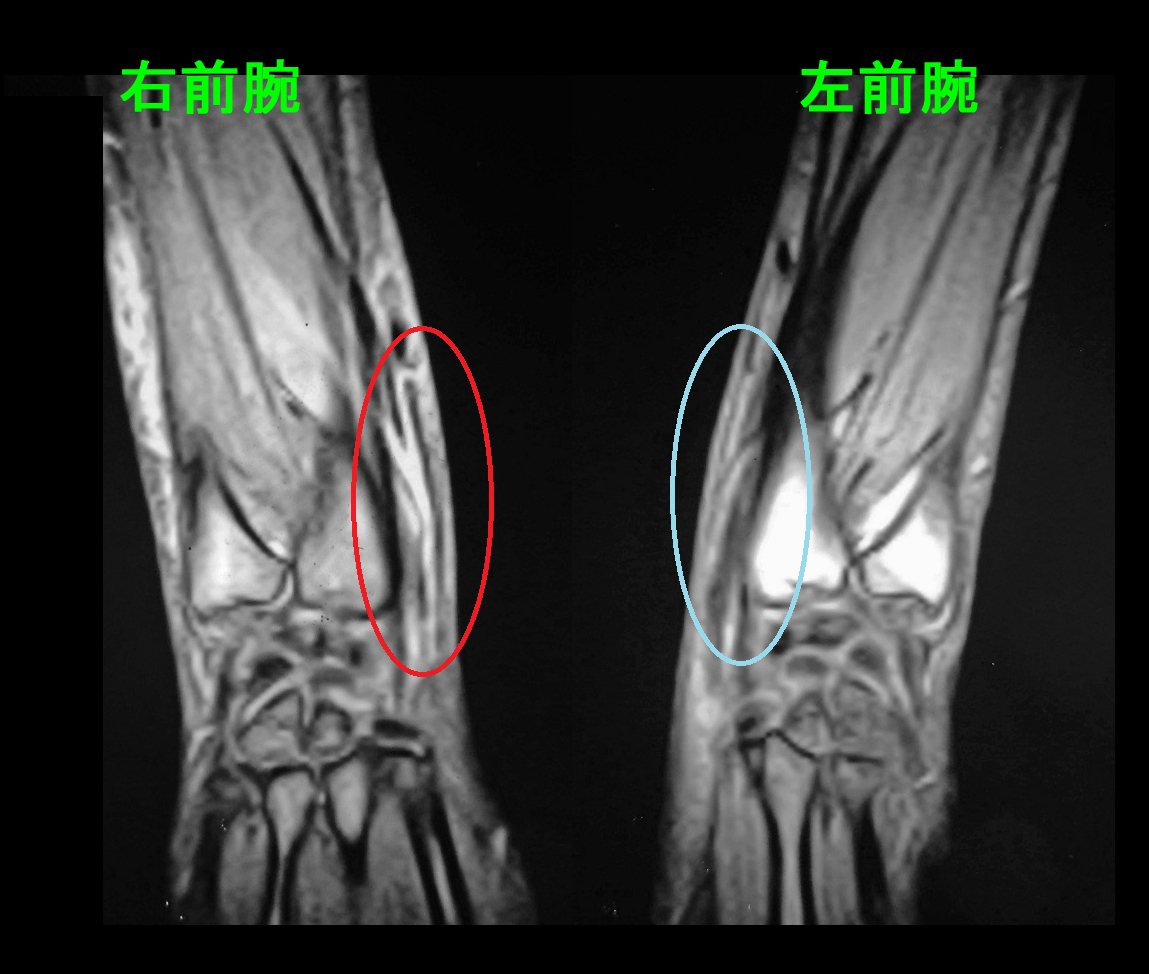

57才男MR2.jpg

このMRI所見は腱の炎症部分を水平に切った断面となりますが、赤丸領域で2本の腱の上に1本の腱(母指外転筋腱)が交差しており、その周囲が白く炎症の状態にあります。

もう1例、提示します。58才の女性です。平成12年2月25日右手関節近傍痛で受診され、書字もできないということで受診されました。

平成12年1月より1日6時間のコンテナの洗浄のパート業務に就労しました。2月半ばに右手関節近傍痛が発症し、2月25日には書字も困難となり、当院を受診しました。

MRI所見は57才の男性と同じで、前腕遠位部に手関節伸筋腱周囲は白く炎症所見が確認されます。

プロカインとケナコルトの局注で症状は治癒しました。

2年後に腰痛で受診されましたが、パートで同じ作業を続けているとのことでした。症状の再発はなかったとのことです。